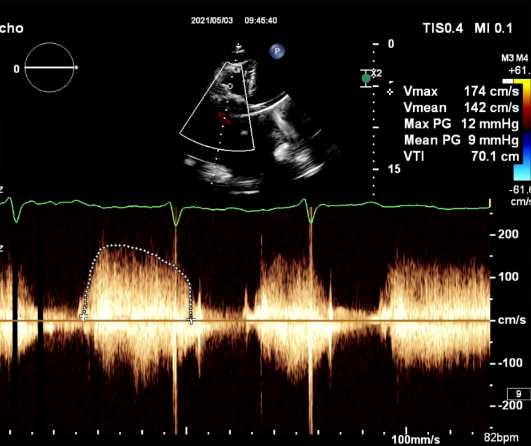

食道超声评估

三尖瓣术前平均压差9mmHg

三尖瓣瓣中瓣术后平均压差3mmHg

术前TTE-TV生物瓣狭窄